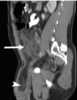

Omental hernia

A paraumbilical (or umbilical) hernia is a hole in the connective tissue of the abdominal wall in the midline with close approximation to the umbilicus. If the hole is large enough there can be protrusion of the abdominal contents, including omental fat and/or bowel. [Source: Wikipedia ]